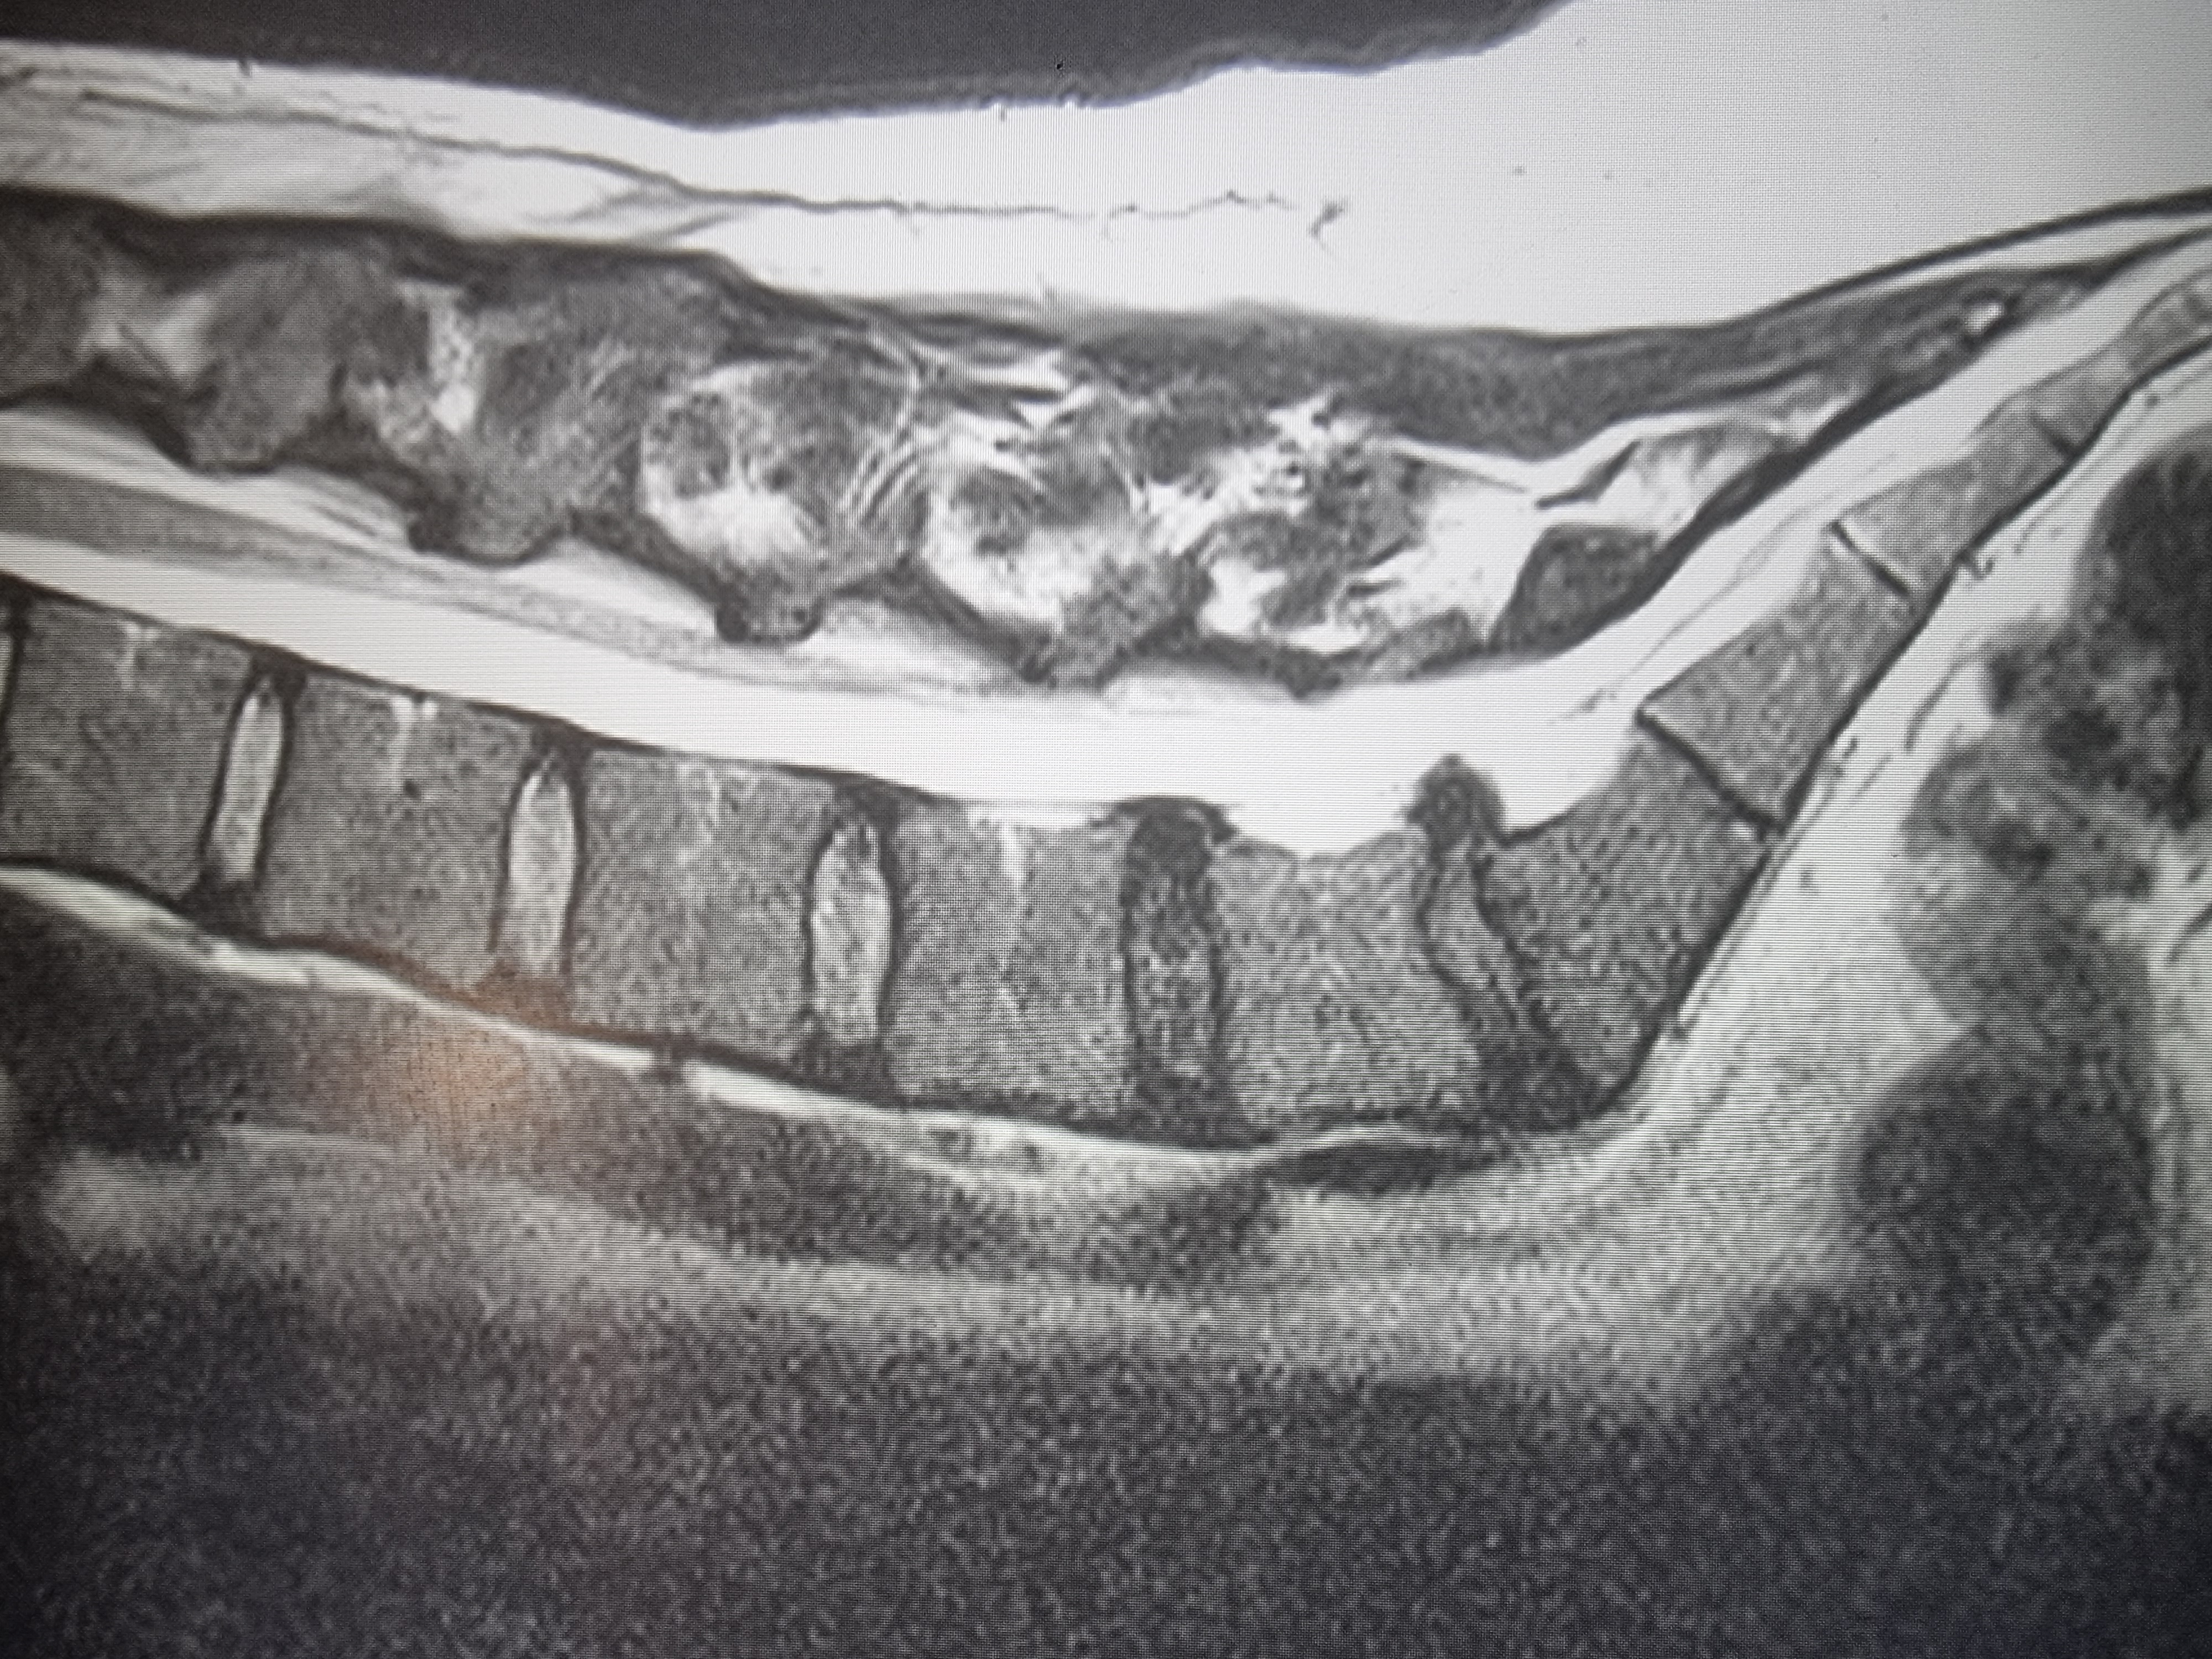

Screenshot20231[...].jpg 414Кб, 2340x1080

Screenshot20231[...].jpg 482Кб, 2340x1080

Боя, я в ахуе, вы в каком веке живёте. Есть такая штука как КЛКТ, стоит копейки, делается 2 минуты. Является золотым стандартном диагностики ЛЮБЫХ зубных пиздецом, там в 3д видно все - кисты, периодонтиты, состояние пазух и тд. Любой приличный врач а) не станет производить серьёзных манипуляций без таких снимков б) спокойно все увидит и распишется где и из за чего у вас болит. Нет бля ходят что-то лечат неизвестно что, не могут определить что и где у них болит, вы ебанутые?